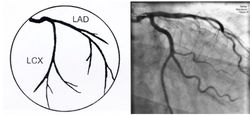

冠状动脉走行于心脏表面,环绕心脏分布,主要有两大分支:左冠状动脉和右冠状动脉。

➤左冠状动脉主干(LM)起源于升主动脉左后方的左冠窦,行至前室间沟时分为左前降支(LAD)和左回旋支(LCX)。

✓前降支通常供应部分左室、右室前壁及室间隔前2/3的血液,其分支分别向三个方向发出,即对角支(D)、右室前支、室间隔支。